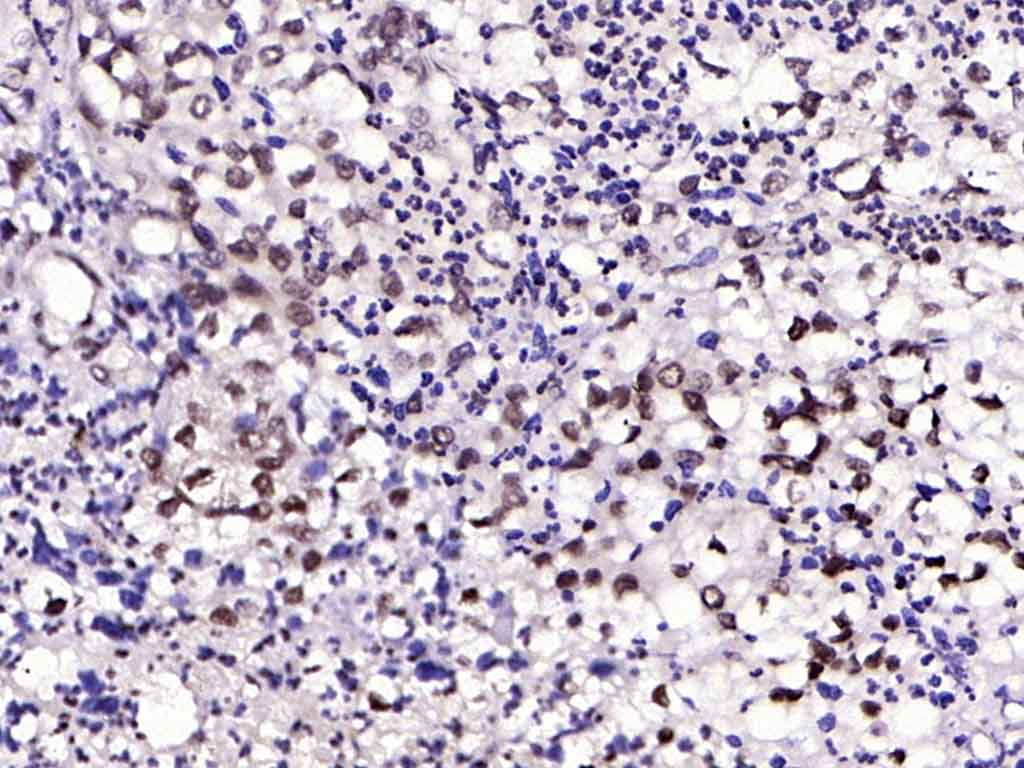

| 产品应用 | IHC-P=1:100-500, IHC-F=1:100-500, ICC/IF=1:100-500, IF=1:100-500, Flow-Cyt=2ug/Test Not yet tested in other applications. |

| {IHC-P} | {1:100-500} |

| {IHC-F} | {1:100-500} |

| {ICC/IF} | {1:100-500} |

| {IF} | {1:100-500} |